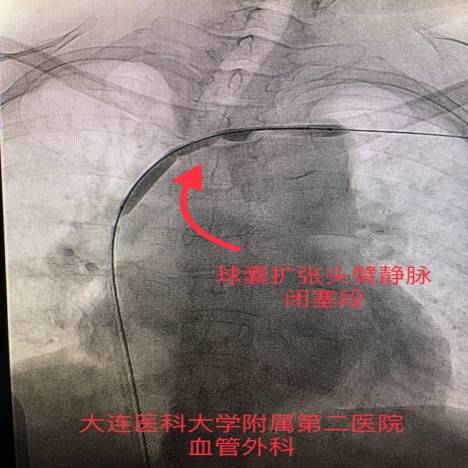

手术过程:造影证实为左侧头臂静脉闭塞。经球囊扩张成形术后,症状完全缓解,内瘘恢复正常使用。

图:造影证实左侧头臂干静脉闭塞

图:球囊扩张左侧头臂干静脉闭塞段